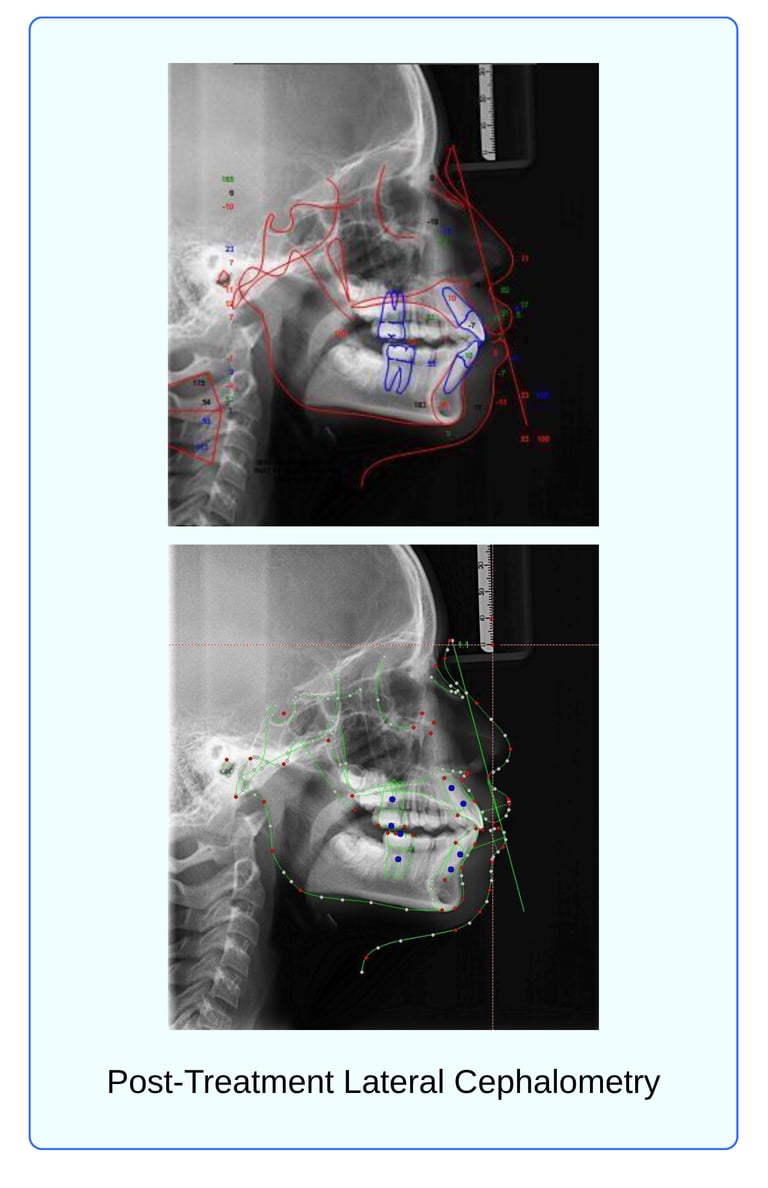

The cephalometric findings reveal significant skeletal, dental, and soft tissue improvements. Skeletally, the maxilla showed forward movement, with SNA increasing from 82.6° to 85° and A-Na perpendicular decreasing from +5 mm to 3.1 mm, indicating a shift toward normal.

Maxillary effective length increased from 90 mm to 93 mm. The mandible also advanced, as evidenced by an increase in SNB from 74° to 80°, and Pog-NA perpendicular improved from -5 mm to -1.1 mm. Mandibular effective length increased from 100 mm to 104 mm. ANB reduced from +7° to +5.7°, and Wits appraisal improved from +4 mm to 0.6 mm, reflecting a more balanced anteroposterior skeletal relationship.

In the vertical dimension, FMA increased from 18° to 21.3°, SN-MP from 25.3° to 29.3°, and Y-Axis from 58° to 68.2°, indicating vertical growth and mandibular clockwise rotation. LAFH/TAFH increased from 50% to 52%, while PFH/AFH decreased from 71.2% to 67.7%, suggesting a slight increase in lower anterior facial height.

Dental:

Dentally, upper incisor proclination decreased (U1–PP from 126° to 109°), while lower incisor proclination increased (L1–MP from 103° to 113°), resulting in a greater interincisal angle (U1–L1 from 105° to 112°). Upper incisor position improved relative to A-perpendicular (from 9 mm to 6.5 mm), and lower incisor position relative to A–Pog increased from 3.2 mm to 5 mm.

Soft Tissue:

Soft tissue analysis showed a more harmonious facial profile, with facial convexity decreasing from 16° to 12.8°. The nasolabial angle remained unchanged at 80°, still below the ideal range. Both upper and lower lips became less protrusive relative to the E-plane, reducing from +3.4 mm to +2.6 mm. Overall, the changes reflect significant skeletal advancement, dental compensation, and profile improvement